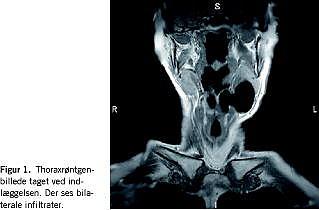

II. En 62-årig kvinde blev henvist af egen læge til en øre-næse-hals-afdeling pga. afoni og blød udfyldning på venstre side af halsen. En MR-skanning viste kombineret laryngocele (Figur 1 ).